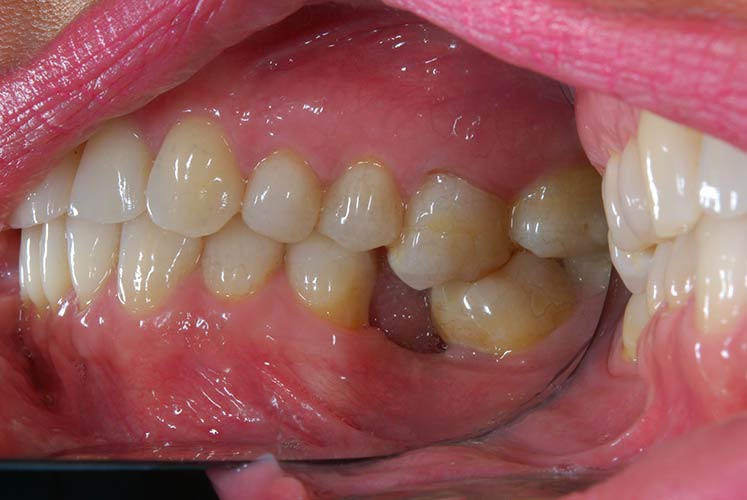

Trattamento ortodontico nell'adulto con intrusione del I° molare superiore mediante l'utilizzo di mini impianti